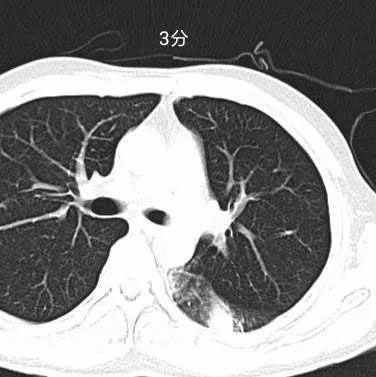

0分:肺部CT无异常征象。

1分:少许钙化,肺大泡,小结节等。

临床意义:与新型冠状病毒(2019-nCoV)感染无相关性。

下图为评分图解